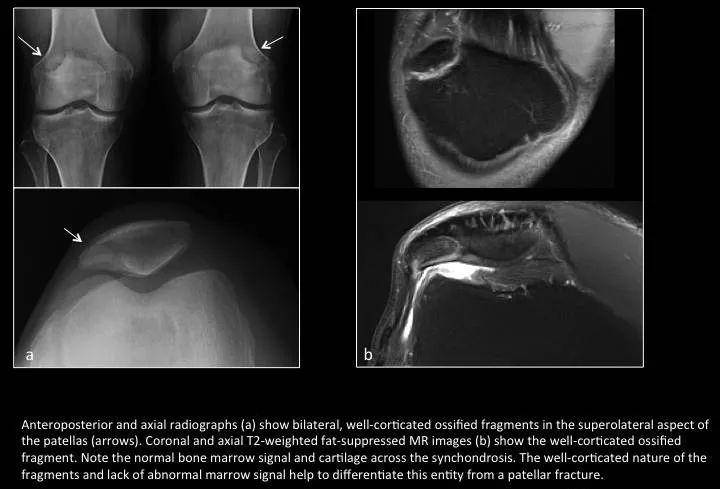

Fig. 5: Bipartite patella

图5:二分髌骨